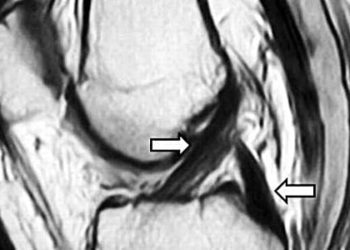

Image: PD